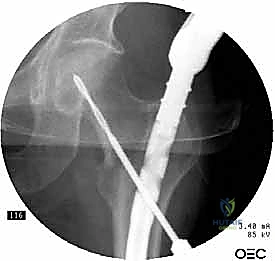

2. الرد المغلق (Closed Reduction)

باستخدام جهاز الأشعة السينية المرئية المستمرة (C-Arm Fluoroscopy) داخل غرفة العمليات، يقوم الدكتور هطيف بإعادة العظام المكسورة إلى محاذاتها التشريحية الصحيحة عن طريق الشد والتدوير الخارجي للساق، وكل ذلك يتم مراقبته على الشاشة بدقة متناهية.

3. إحداث الشق الجراحي ونقطة الدخول

من خلال شق جراحي صغير جداً (حوالي 3 إلى 5 سم) أعلى الفخذ (فوق المدور الكبير)، يتم الوصول إلى قمة عظمة الفخذ. يتم إدخال سلك دليلي (Guide Wire) دقيق لتحديد نقطة الدخول المثالية للقناة النخاعية.

4. توسيع القناة وإدخال المسمار

يتم استخدام أدوات حفر خاصة (Reamers) لتوسيع القناة النخاعية بلطف لتستوعب المسمار المصنوع من التيتانيوم. بعد ذلك، يتم انزلاق المسمار النخاعي الرئيسي داخل العظم حتى يصل إلى العمق المطلوب.

5. تثبيت عنق ورأس الفخذ (المسمار الرأسي)

من خلال ذراع توجيه متصلة بالمسمار الرئيسي، يتم إحداث ثقب في عنق ورأس عظمة الفخذ. يتم إدخال المسمار الرأسي (Cephalic Screw) السميك ليمسك برأس الفخذ بقوة ويسحبه نحو المسمار الرئيسي، مما يضغط الكسر (Compression) ويحفز التئام العظام بسرعة.

6. التثبيت السفلي (Distal Locking)

لضمان عدم دوران العظمة حول المسمار، يتم إدخال مسمار أو مسمارين صغيرين في الجزء السفلي من المسمار النخاعي عبر شقوق جلدية دقيقة جداً (لا تتجاوز 1 سم).